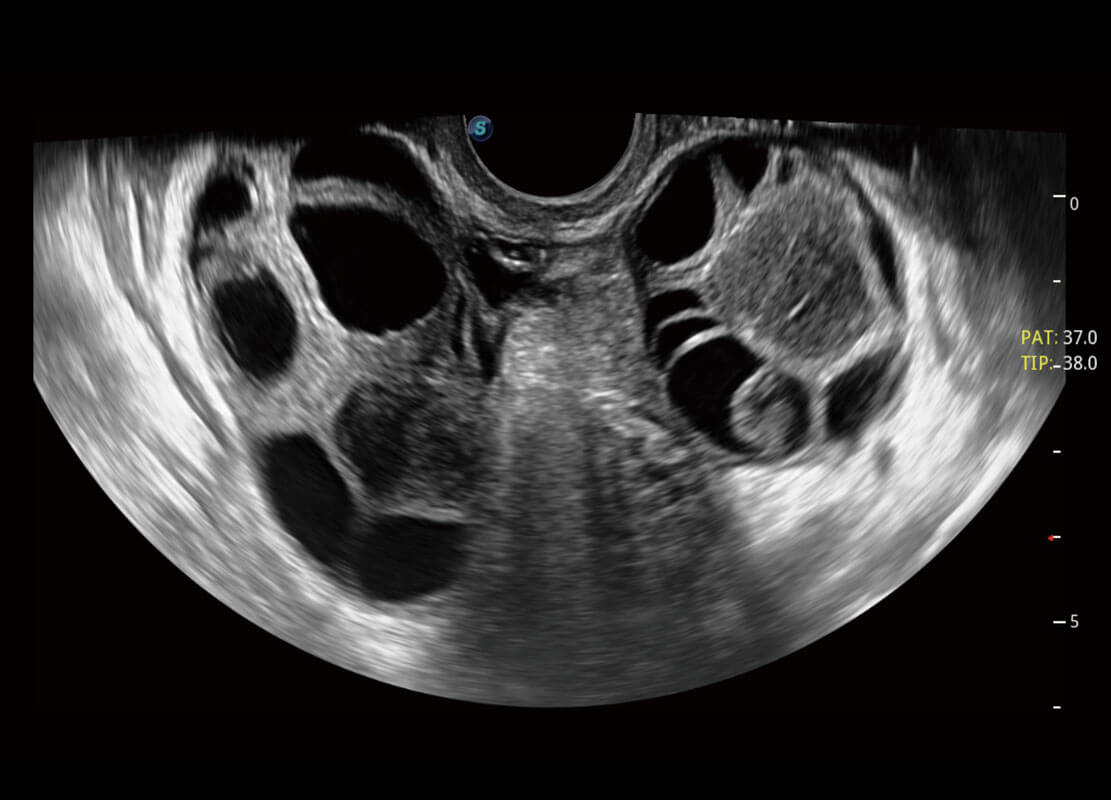

腔内妇科-宫腔分离

腔内妇科-卵巢

腔内三维-宫内节育器

腔内三维-光影成像

P60优异的图像质量搭载专科探头,在妇科基础疾病的诊断、卵泡生长的监测、输卵管通畅情况的判别等方面为您提供生殖应用方案。